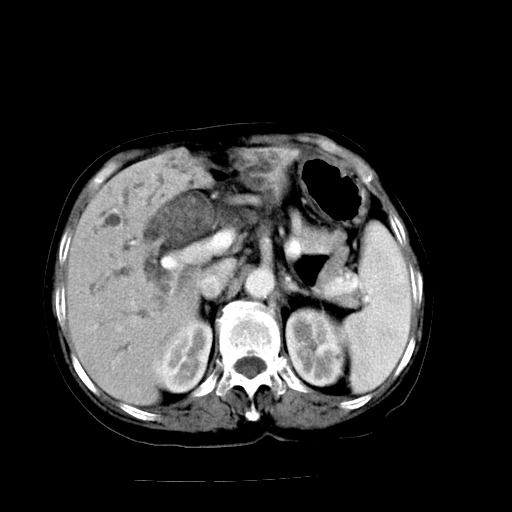

以下是引用随光逐影在2009-4-7 8:21:00的发言:[br]肝内外胆管多发性结石并肝内外胆管扩张;胆系感染。